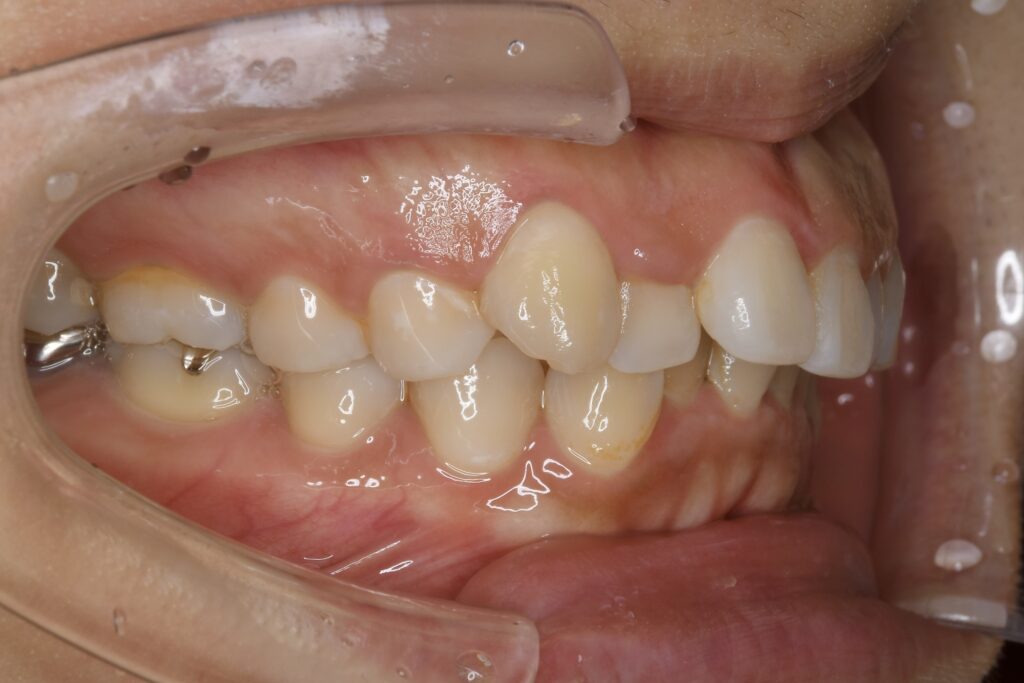

32歳 女性 治療期間:1年7ヶ月

AFTER

診断名・主な症状 叢生を伴う上顎前突

治療内容 上下とも歯を2本抜いて、上の前歯を後方に引きながら、でこぼこを治しました。

使用装置 マウスピース矯正装置(インビザライン)

抜歯部位 上 両側4番目

下 右側4番目、左側5番目